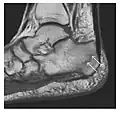

Triquetral fracture usually occurs on the dorsal aspect by impingement from the ulnar styloid or avulsion of strong ligamentous attachment. The dorsal avulsion fracture or "chip fracture" appears as a small bony fragment on the dorsal aspect of the triquetrum and is best detected on the lateral view(Figure 4). When radiography is negative in patients with high suspicion of a fracture, both MRI and MDCT will be of value. However, it has been shown that MRI is superior for detecting trabecular fractures in carpal bones.

-

a -

b

Figure 4: Dorsal triquetral fracture of the left wrist in a 30-year-old man after a trauma. (a) Anteroposterior radiograph shows a normal appearance. (b) Lateral radiograph of the same wrist demonstrates a chip fracture off the dorsal aspect of the triquetrum (arrow).[1]